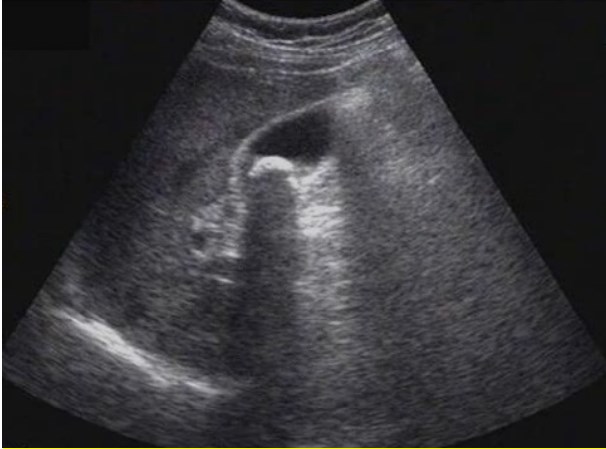

試題:患者女性,50歲,間斷上腹隱痛半年,診斷為(2分)

A.肝癌

B.肝硬化

C.膽囊結(jié)石

D.腎結(jié)石

【答案】C